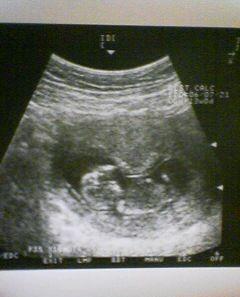

13日は定期健診の日で、会社にお休みをもらい、一ヶ月振りにいってきました。予約はしてるものの、案の定一時間近く待たされ、検診をしてもらいました。今回から、超音波もおなかの上から診てもらい元気に育っているようです。心臓もトクトクと動いてるのが見てとれました(*^。^*)もうしっかり、頭と体が作られていました。今更ながら、このおなかにいてるのが不思議です・・・今回の写真では詳しい大きさがのってないのですが、13wだとおよそ10cm位だということです。そろそろつわりも治まる時期のはずですが、最近、以前とはまた違った感じで、気持ち悪くてまだ抜け出せません・・・・(-"-)が、食欲はあって食べれるので、お医者さんに言っても「食べれなくなったら、言ってきてください(*^。^*)」と、簡単に返されました・・・いつまで我慢すればいいのだでもま、順調に育ってくれてるのだから、よしとしよう・・・では、ちょっと見にくいですが、赤ちゃんの写真です。ご協力お願いします。↓HOMEへ